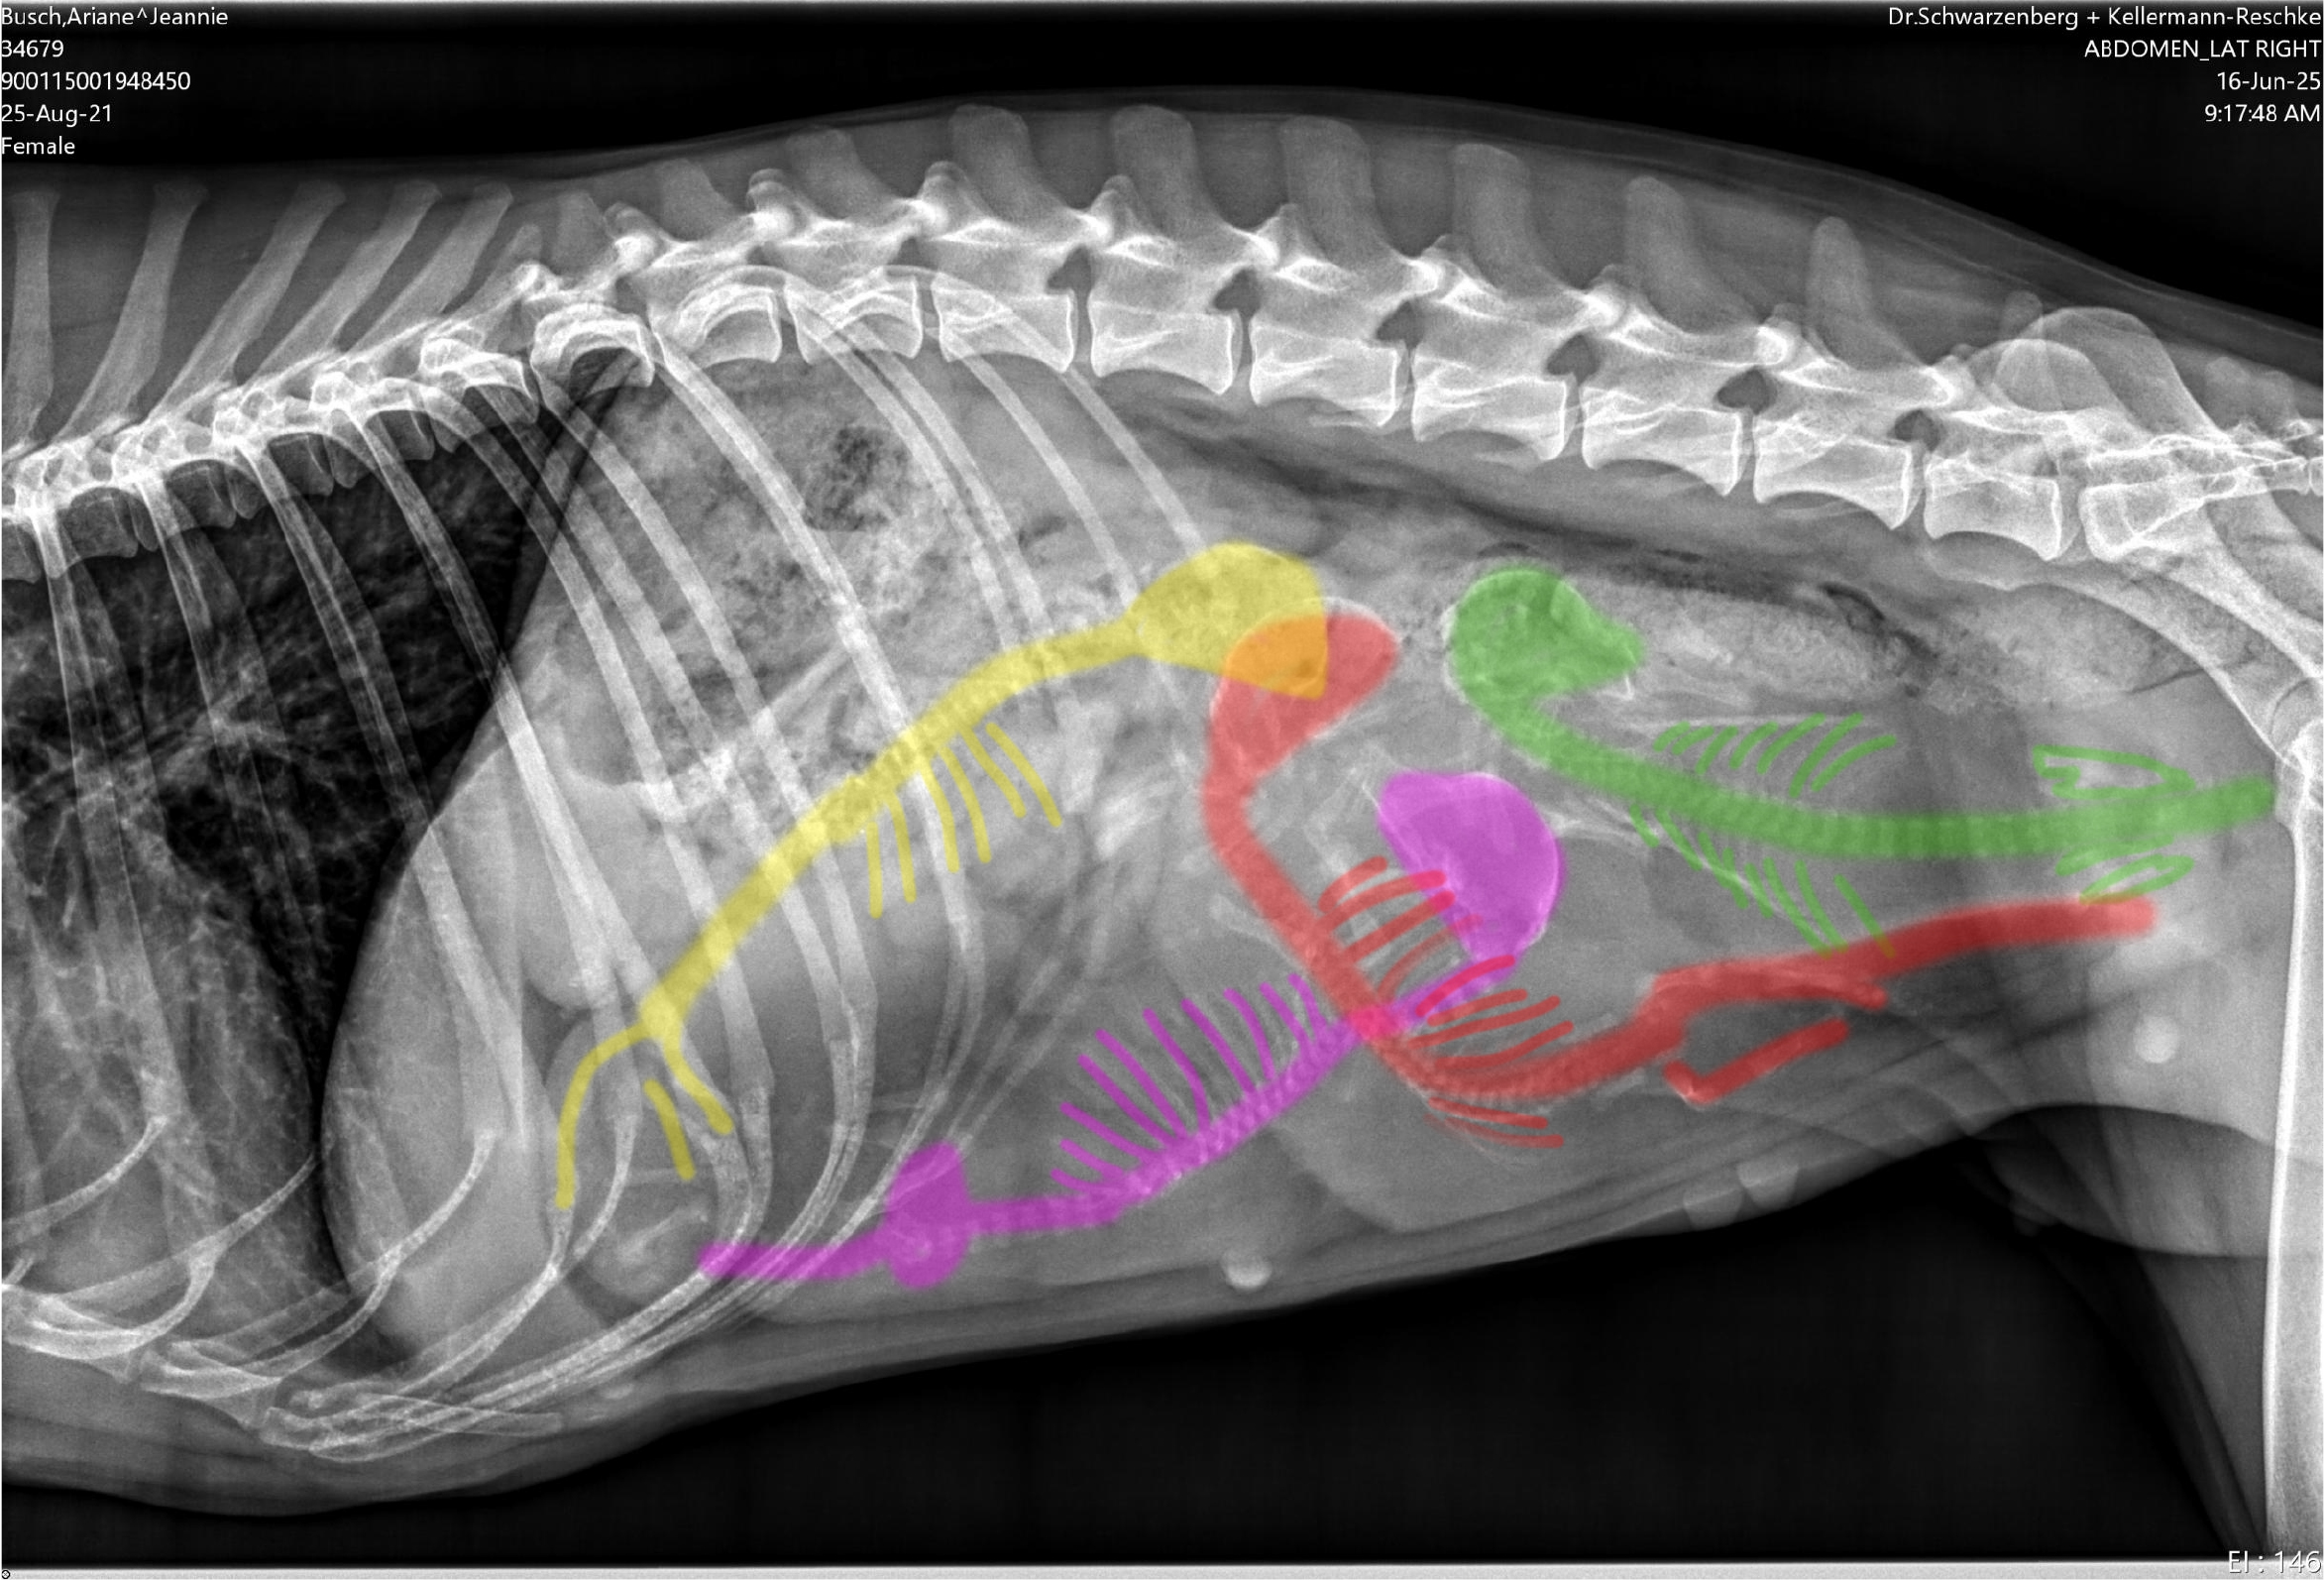

Unsere bezaubernde Jeannie „Tova‘s Riesling Surprise in Germany“ wurde Ende April von unserem charmanten Mio „Golden Nugget's Achilles“ gedeckt.

Wir erhoffen uns von dieser Verpaarung von zwei F3 Windsprites eine Erhöhung der genetischen Diversität mit den damit verbundenen positiven Auswirkungen auf die langfristige Gesundheit der Rasse. Apropos Gesundheit: Jeannie und Mio sind bereits 3,5 und 5,5 Jahre alt. Bis zur Zulassung der F3 Silken Windsprites hat es ja bekanntlich einige Jahre gedauert. Positiv daran ist, dass wir wissen, dass beide Hunde eine phantastische Konstitution und Gesundheit haben. Beide sind körperlich total fit und wirklich robust und unempfindlich – eigentlich waren sie noch nie richtig krank und vertragen jedes Futter.